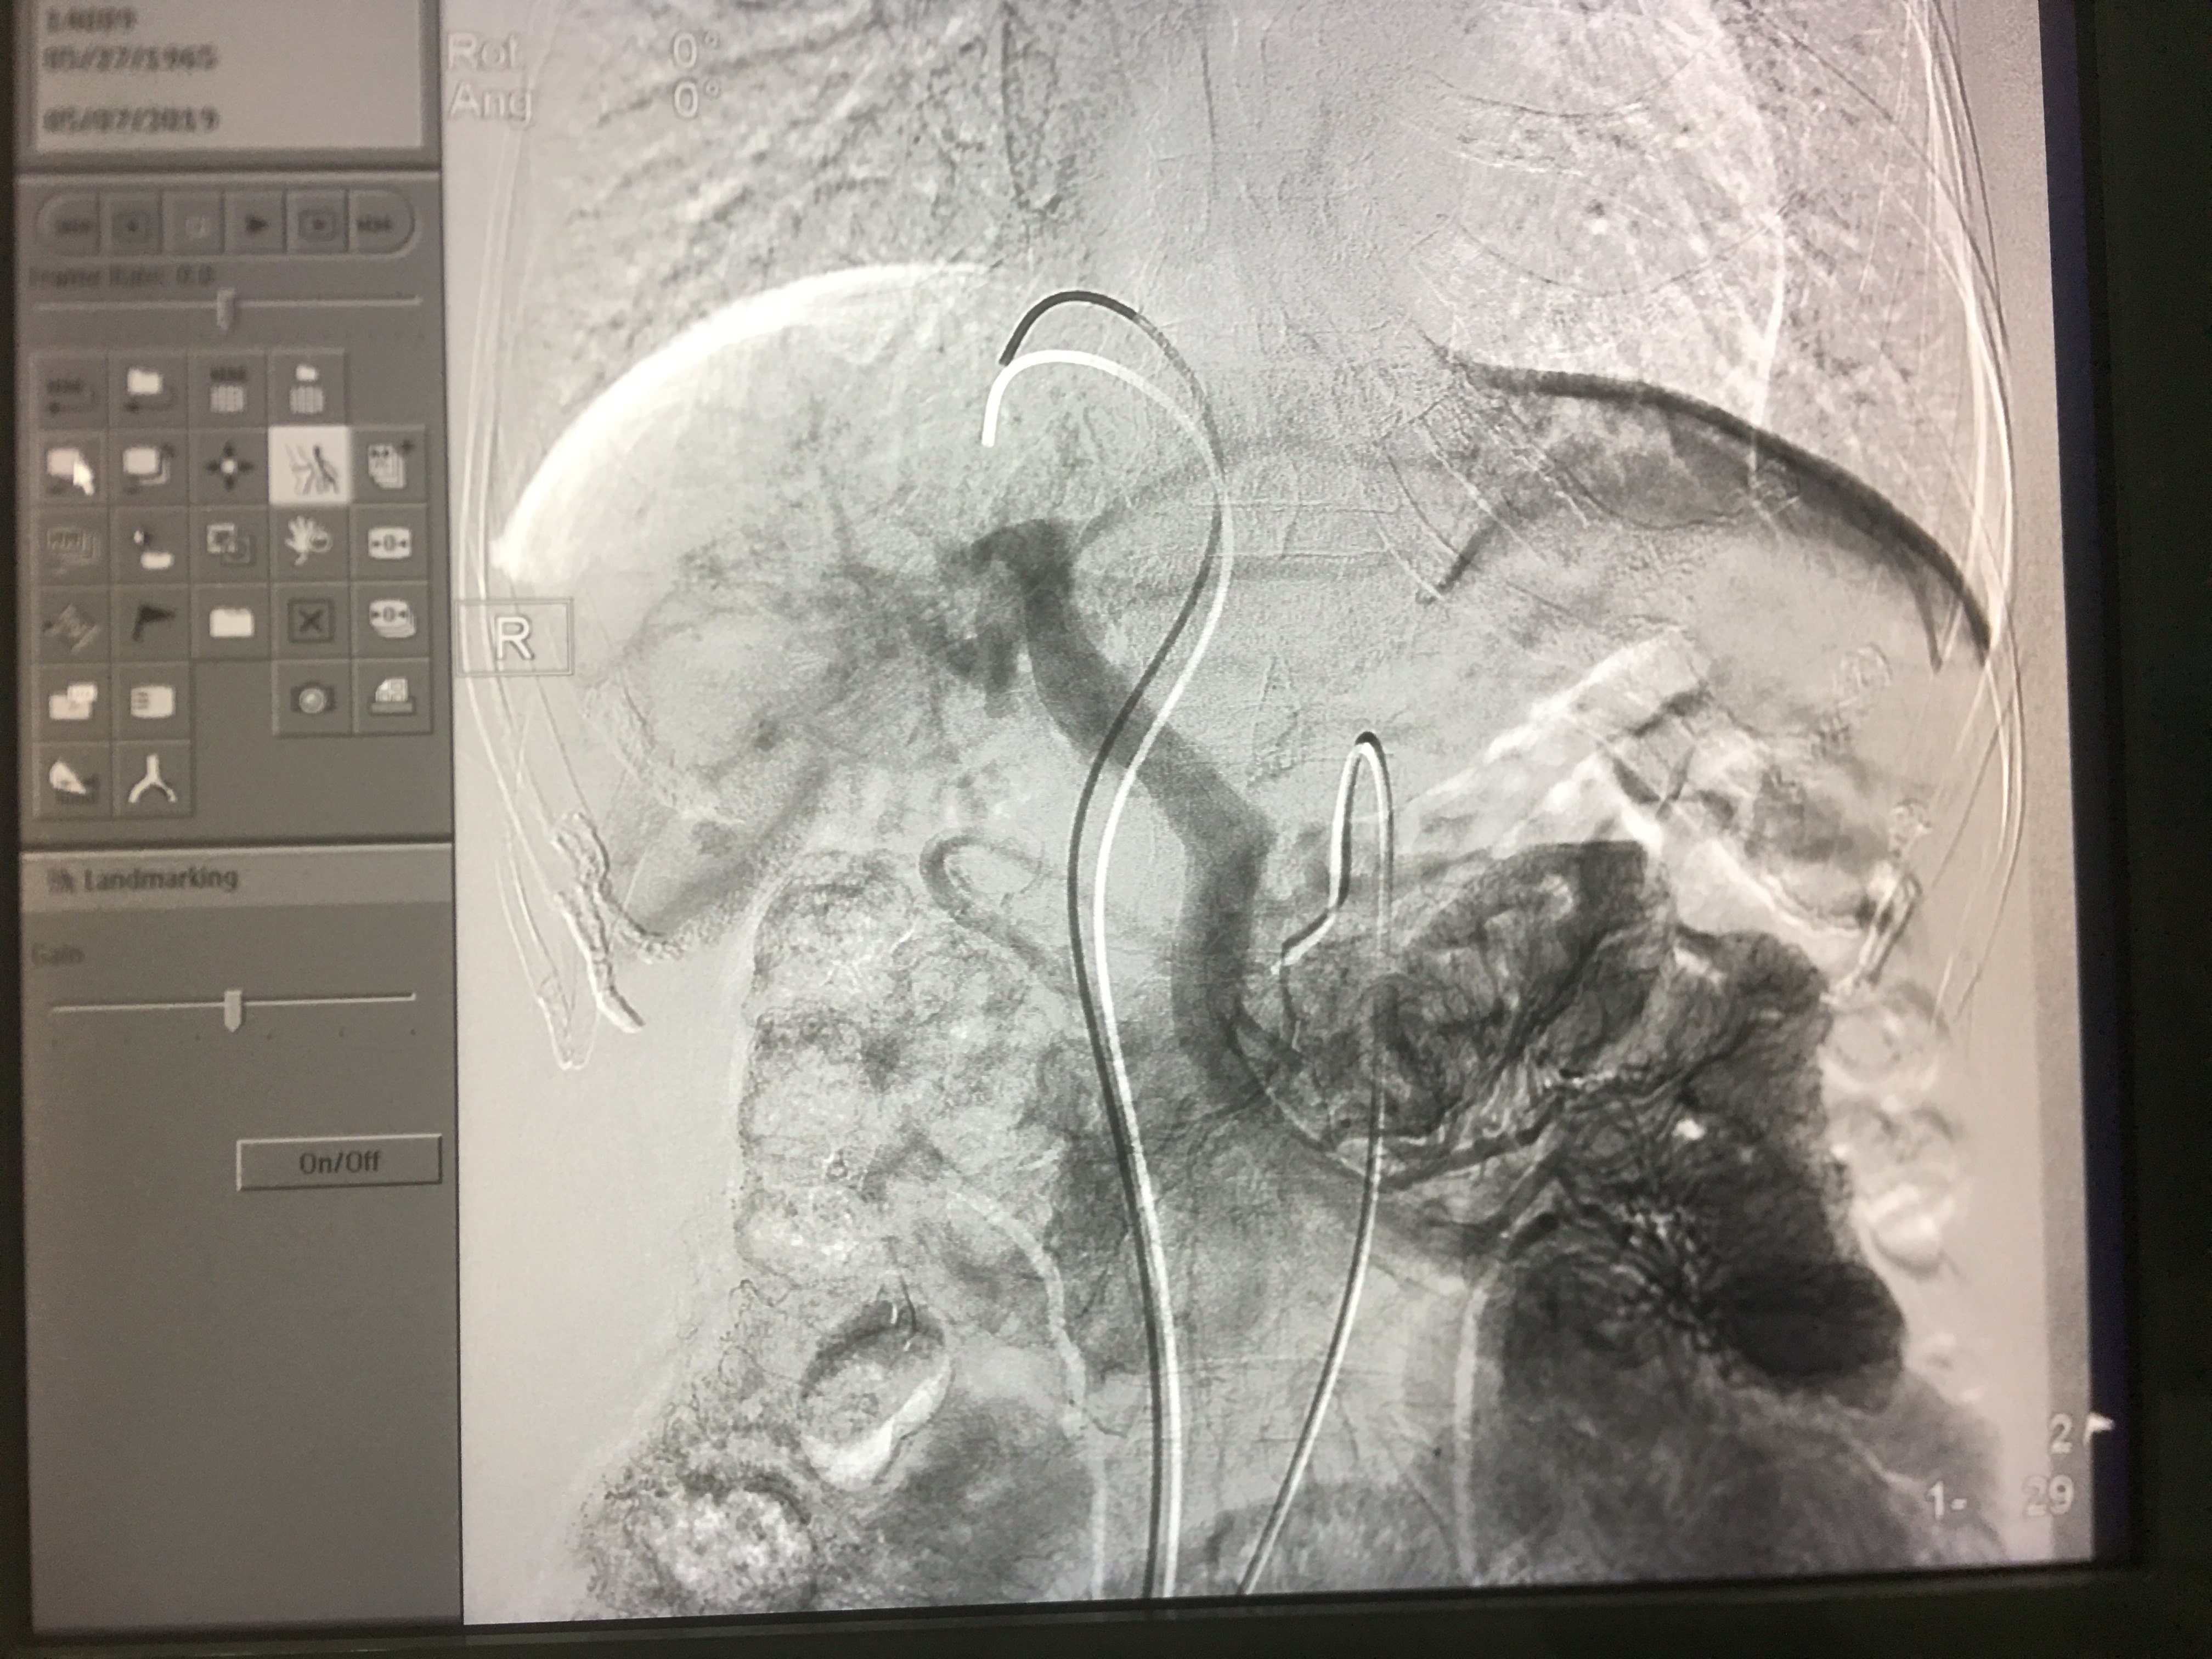

间接门静脉造影以期获得肝静脉和门静脉之间的关系。